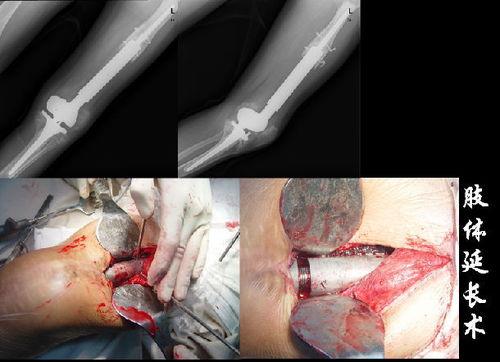

骨肉瘤的治疗过程异常艰辛。小雅告诉我,她曾经经历了多次手术,每一次都像是在与死神搏斗。手术后的放疗、化疗更是让她痛苦不堪。但她从未放弃,她说:“我知道,只有坚持下去,才能看到希望的曙光。”